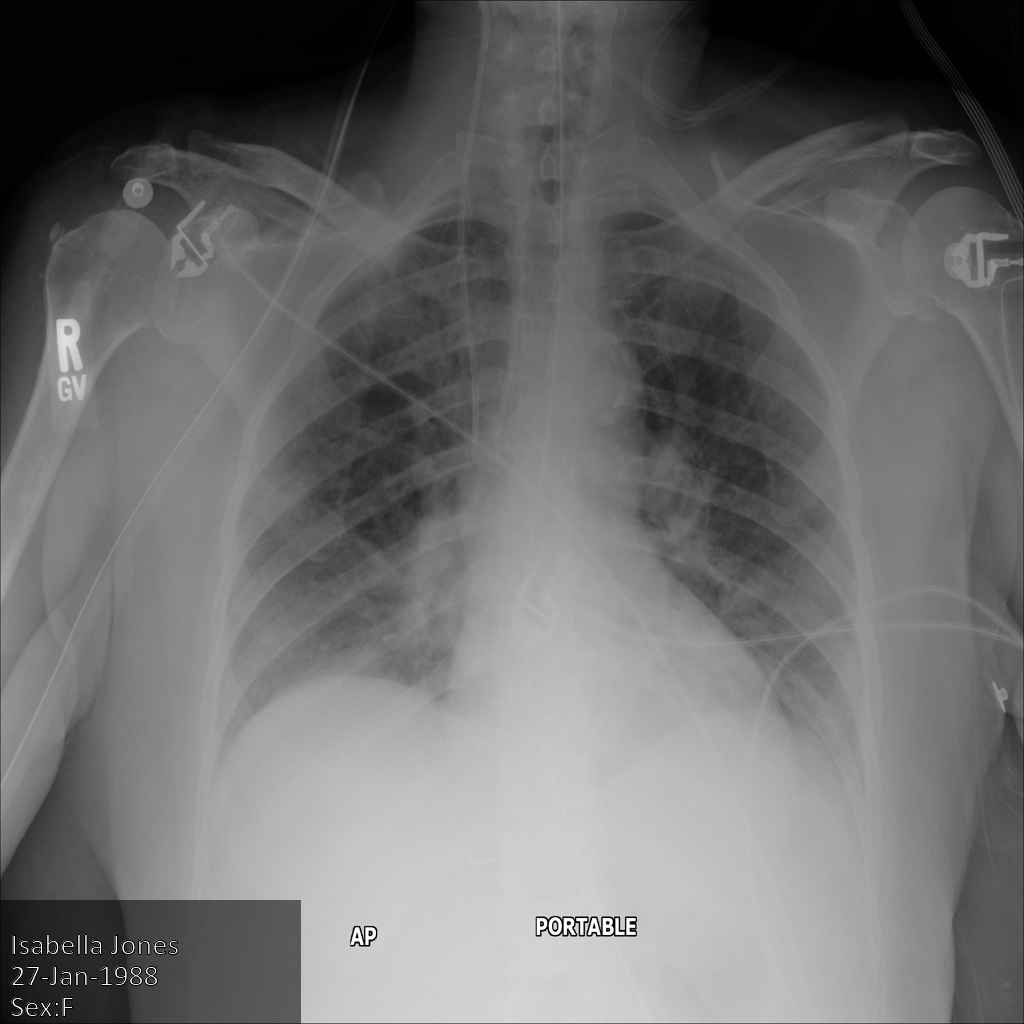

Chacune des sections suivantes fournit des exemples d'anonymisation de données DICOM à l'aide de différentes méthodes. Une sortie de l'image anonymisée est fournie avec chaque échantillon. Chaque exemple utilise l'image d'origine suivante comme entrée :

Vous pouvez comparer l'image de sortie de chaque opération d'anonymisation à cette image d'origine pour voir les effets de l'opération.

Une fois l'image envoyée à l'API Cloud Healthcare, elle apparaît comme suit. Alors que les métadonnées affichées dans les angles supérieurs de l'image ont été masquées, les informations de santé protégées qui sont incluses dans l'angle inférieur de l'image sont conservées. Pour supprimer également le texte incrusté, consultez la section Masquer le texte incrusté dans les images.